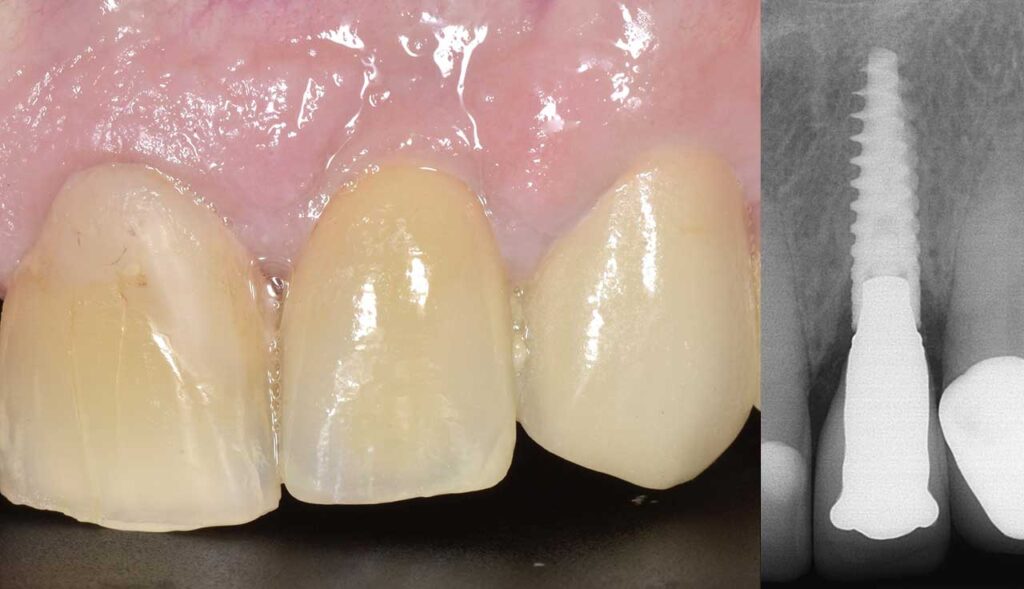

前歯部インプラント

治療後

折れてしまった歯を抜去し、周りの歯に調和したインプラント治療を行いました。